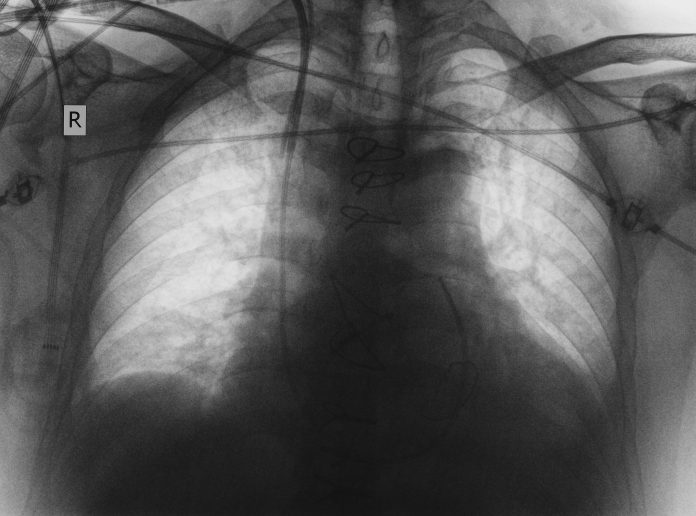

Interstitial lung disease (ILD) is characterised by inflammation and fibrosis which develops as a consequence of taking certain drugs, inhaling antigens or as part of autoimmune connective tissue disease. Idiopathic pulmonary fibrosis (IPF) has no identifiable cause and is the most aggressive form, typified by progressive lung fibrosis and inescapably worsening breathlessness as lung function declines, ultimately leading to death.

Radiological imaging with high-resolution CT scanning may show honeycomb cysts and subpleural reticulation but is not perfect. Newer technology including cryobiopsy as a surgical alternative and computer-based CT image evaluation (data-driven textural analysis) and machine learning may improve the situation.